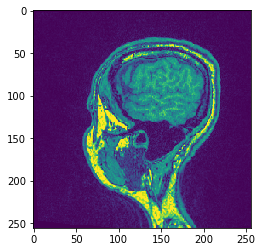

复制切片#

为了可视化特定的切片,而不让图像离开GPU内存,请使用copy_slice方法。

# Copy Slice

image_slice = cle.create([256, 256]);

slice_z_position = 40.0;

cle.copy_slice(input_image, image_slice, slice_z_position)

# show result

cle.imshow(image_slice)

../_images/c60c6141e977151383e4e4988e95e2b2a8a313b44d0ead1d5e0cbcf484394c62.png